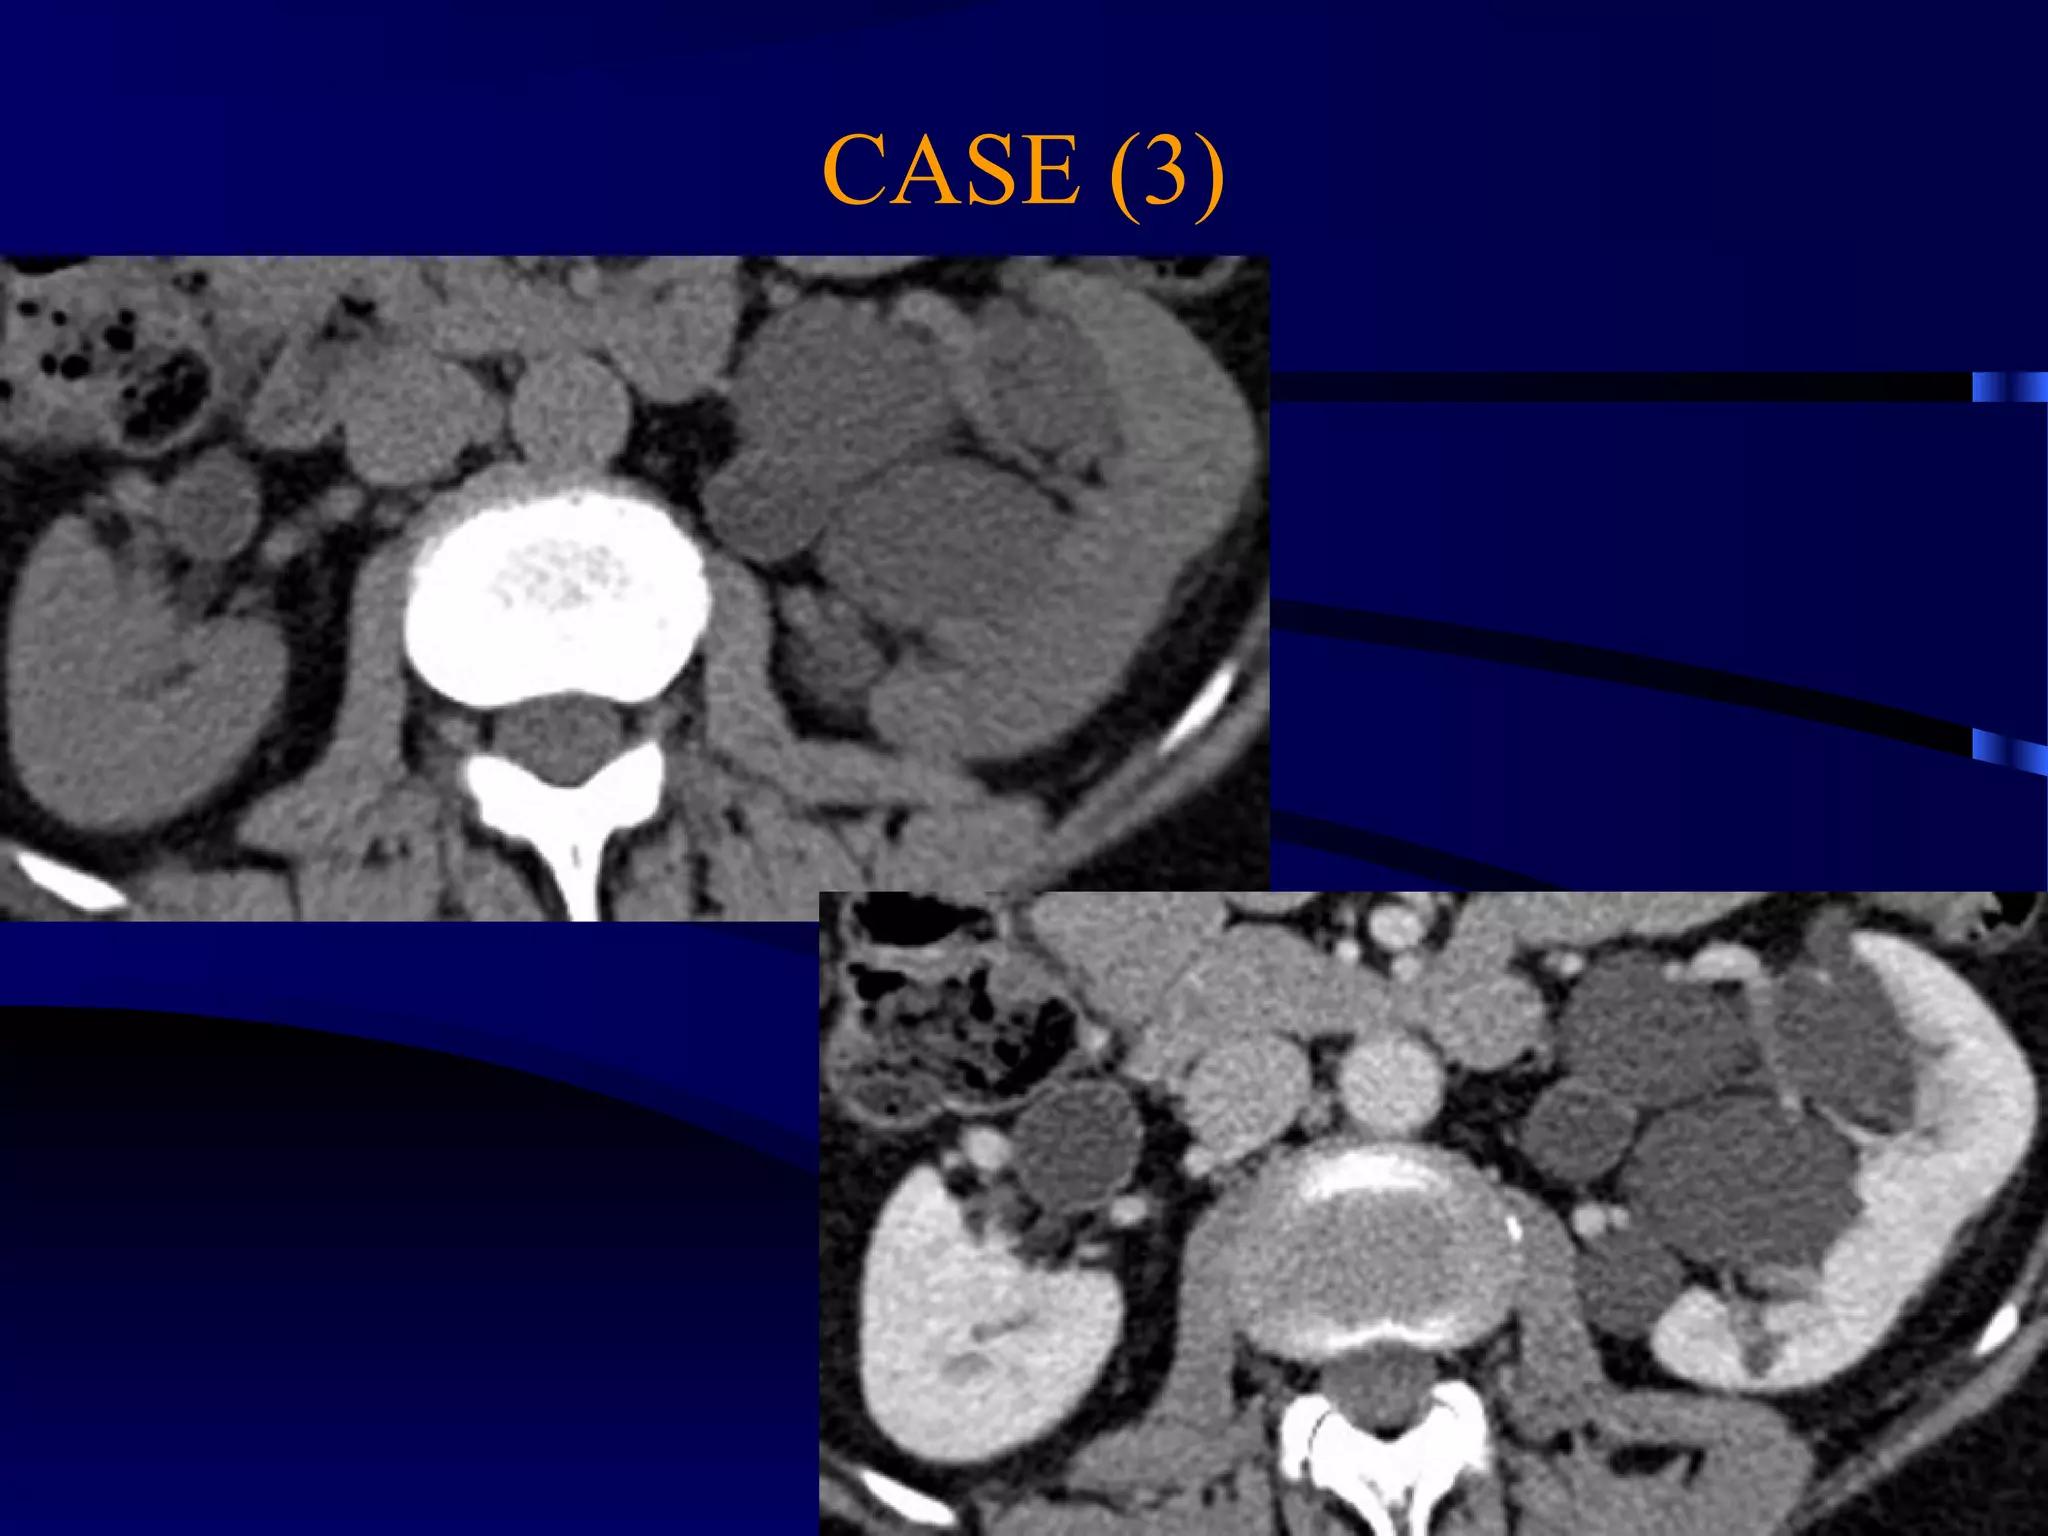

CASE (3)

MULTILOCULAR PARAPELVIC CYST WITH

STRETCHING OF THE MAJOR CALYCES